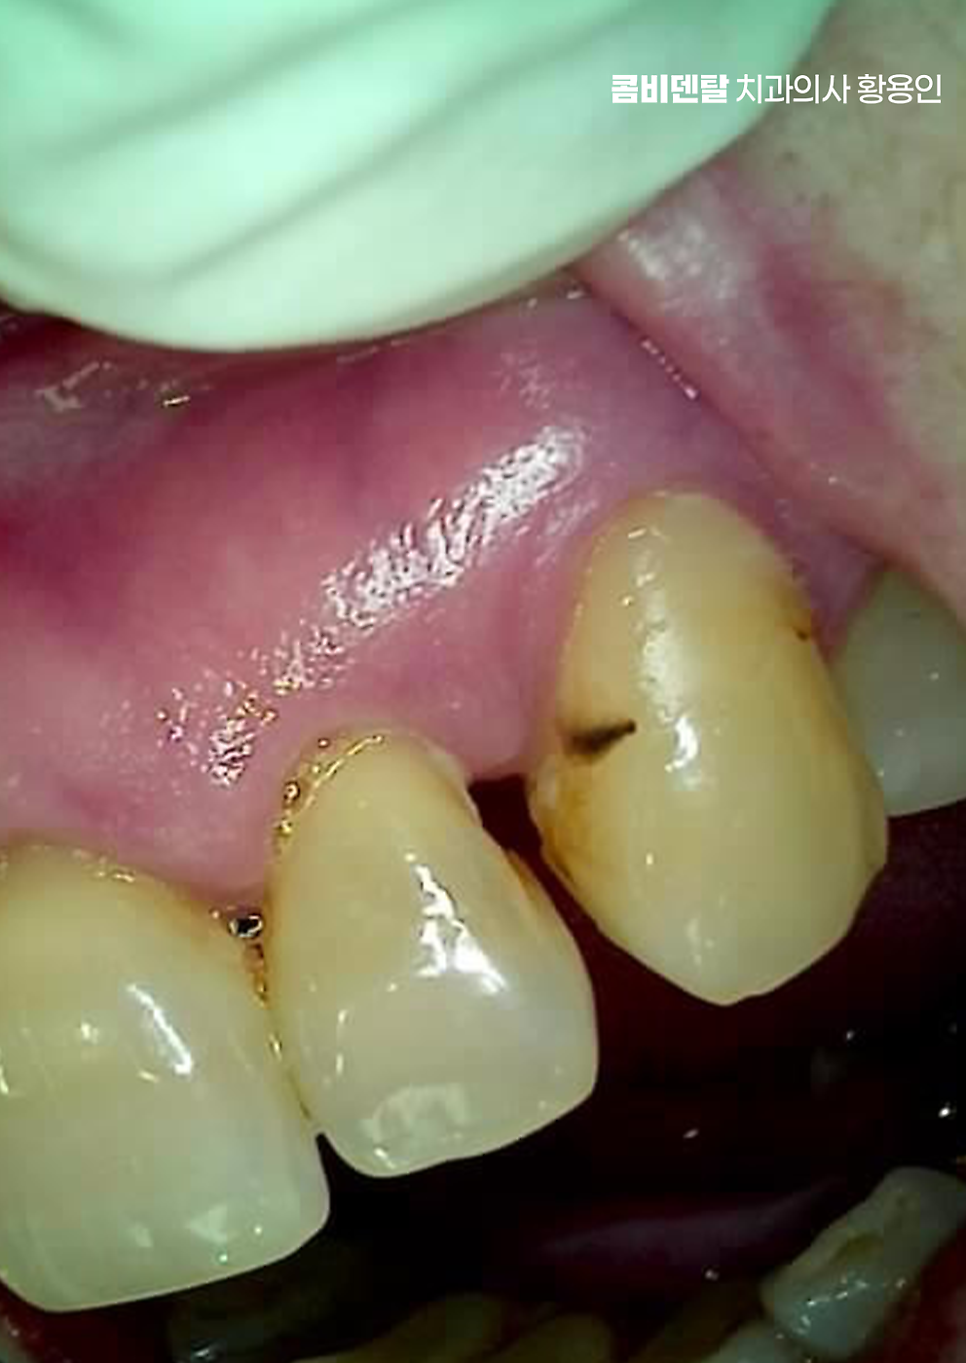

특히 치아 사이에 음식물이 자주 끼거나, 양치를 해도 이물감이 사라지지 않거나, 잇몸이 자꾸 붓고 피가 난다면 이미 치아 사이 벌어짐이 단순한 미용 문제가 아니라 치주적인 구조 손상이 시작됐다는 경고 신호가 될 수 있는데 이때는 ‘치아 사이를 붙이는 교정을 해야 하나?’ 같은 심미적인 접근만이 아니라, 먼저 염증을 잡고 잇몸을 살리는 데 집중하는 게 우선이 될 수 있고 그다음에 기능과 배열을 복원하는 방향으로 치료가 이어져야 할 수 있어요

여기서 기본이 되는 건 스케일링인데 스케일링은 단순히 겉에 붙은 치석을 제거하는 게 아니라, 치아 뿌리 쪽 깊숙한 부위에 붙어 있는 세균성 치태까지 제거해 잇몸 안쪽 염증을 줄이는 데 목적이 있어요. 그런데 잇몸 깊숙이 치석이 침착돼 있거나, 이미 치주낭이라고 하는 염증성 주머니가 형성돼 있다면 단순 스케일링만으로는 부족하고, ‘치근활택술’이라는 보다 깊은 치료가 필요한데 이건 마취 후 치아 뿌리 표면을 매끄럽게 다듬어 세균이 다시 달라붙기 어렵게 만드는 치료로서 이러한 잇몸 치료를 통해 잇몸 조직의 재생을 유도하고, 치아의 흔들림을 줄이게 될 수 있어요

치아 사이 벌어짐의 주된 원인이 잇몸 문제라고 한다면 이러한 잇몸 치료가 선행되어야 하고 그 다음으로 실질적으로 치아 사이가 벌어지면서 발생된 치아 배열이나 치아 사이의 충치 문제 등을 교정 혹은 보철 치료를 통해 해결해야 할 수 있는데요